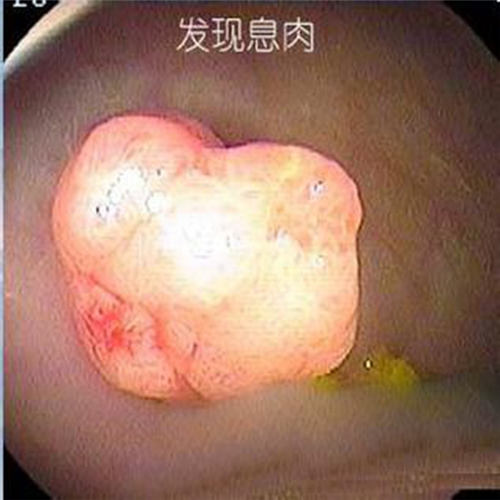

直腸息肉早期

直腸息肉脫出的

直腸息肉脫出